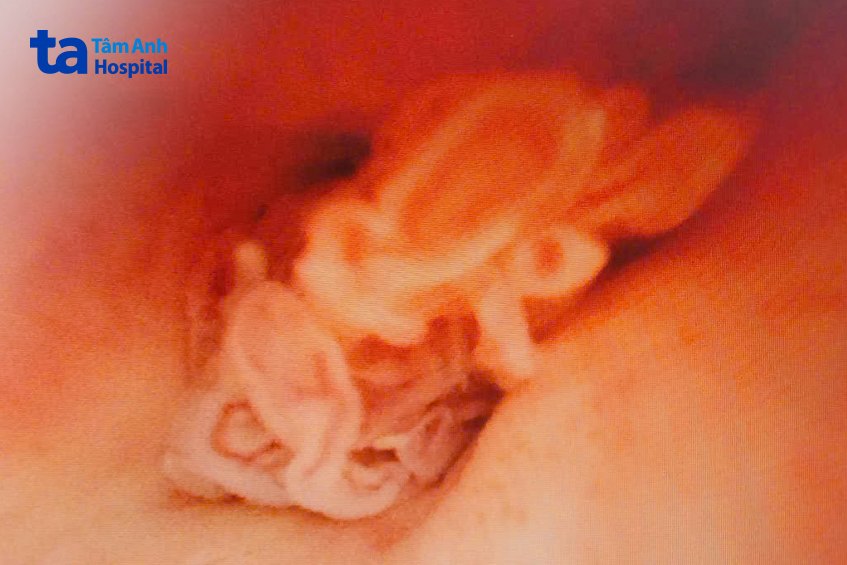

Tiến sĩ bác sĩ Nguyễn Hoàng Đức, Trưởng khoa Tiết niệu, Trung tâm Tiết niệu – Thận học – Nam khoa, Bệnh viện Đa khoa Tâm Anh TP.HCM, chỉ định ông K. nội soi niệu đạo bằng ống mềm tìm nguyên nhân niệu đạo chảy máu. Khi nội soi, bác sĩ nhận thấy trong niệu đạo trước (đoạn niệu đạo nằm trong dương vật) của người bệnh có một số khối u nhỏ, chồi sùi.

Ông K. từng phải mổ cắt toàn bộ bàng quang, tuyến tiền liệt do ung thư niệu mạc, bác sĩ Đức nghi ngờ các khối u xuất hiện trong niệu đạo của ông do ung thư niệu mạc tái phát.